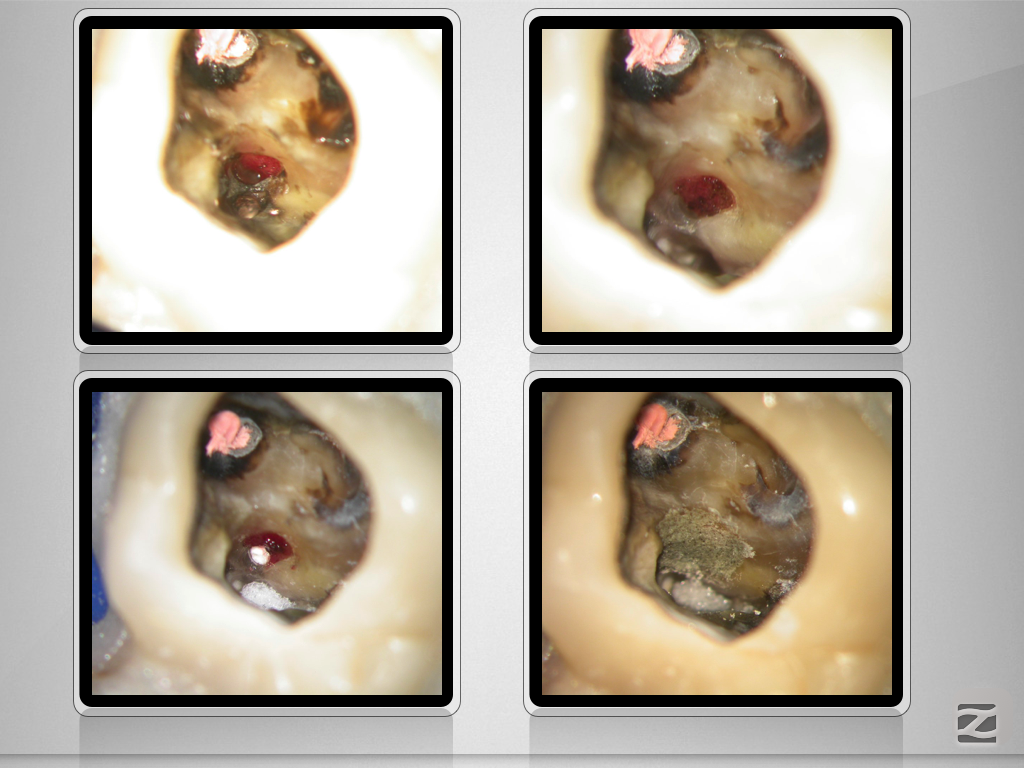

2526d-007

Enter Sandman